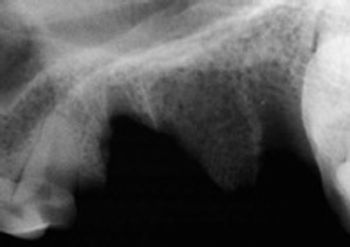

For the last six months, I have been treating a 15-year-old castrated male domestic shorthaired cat with an isolated oral lesion.

When working up inflammatory diseases in the cat, it is important to know that at various stages of the disease process, they can display pathogenic behavior that is similar when compared to one another.

A variety of dental lesions can occur as a result of chronic wear or acute trauma including severe dental attrition, fractured teeth, subluxated teeth, avulsed teeth and jaw fractures.